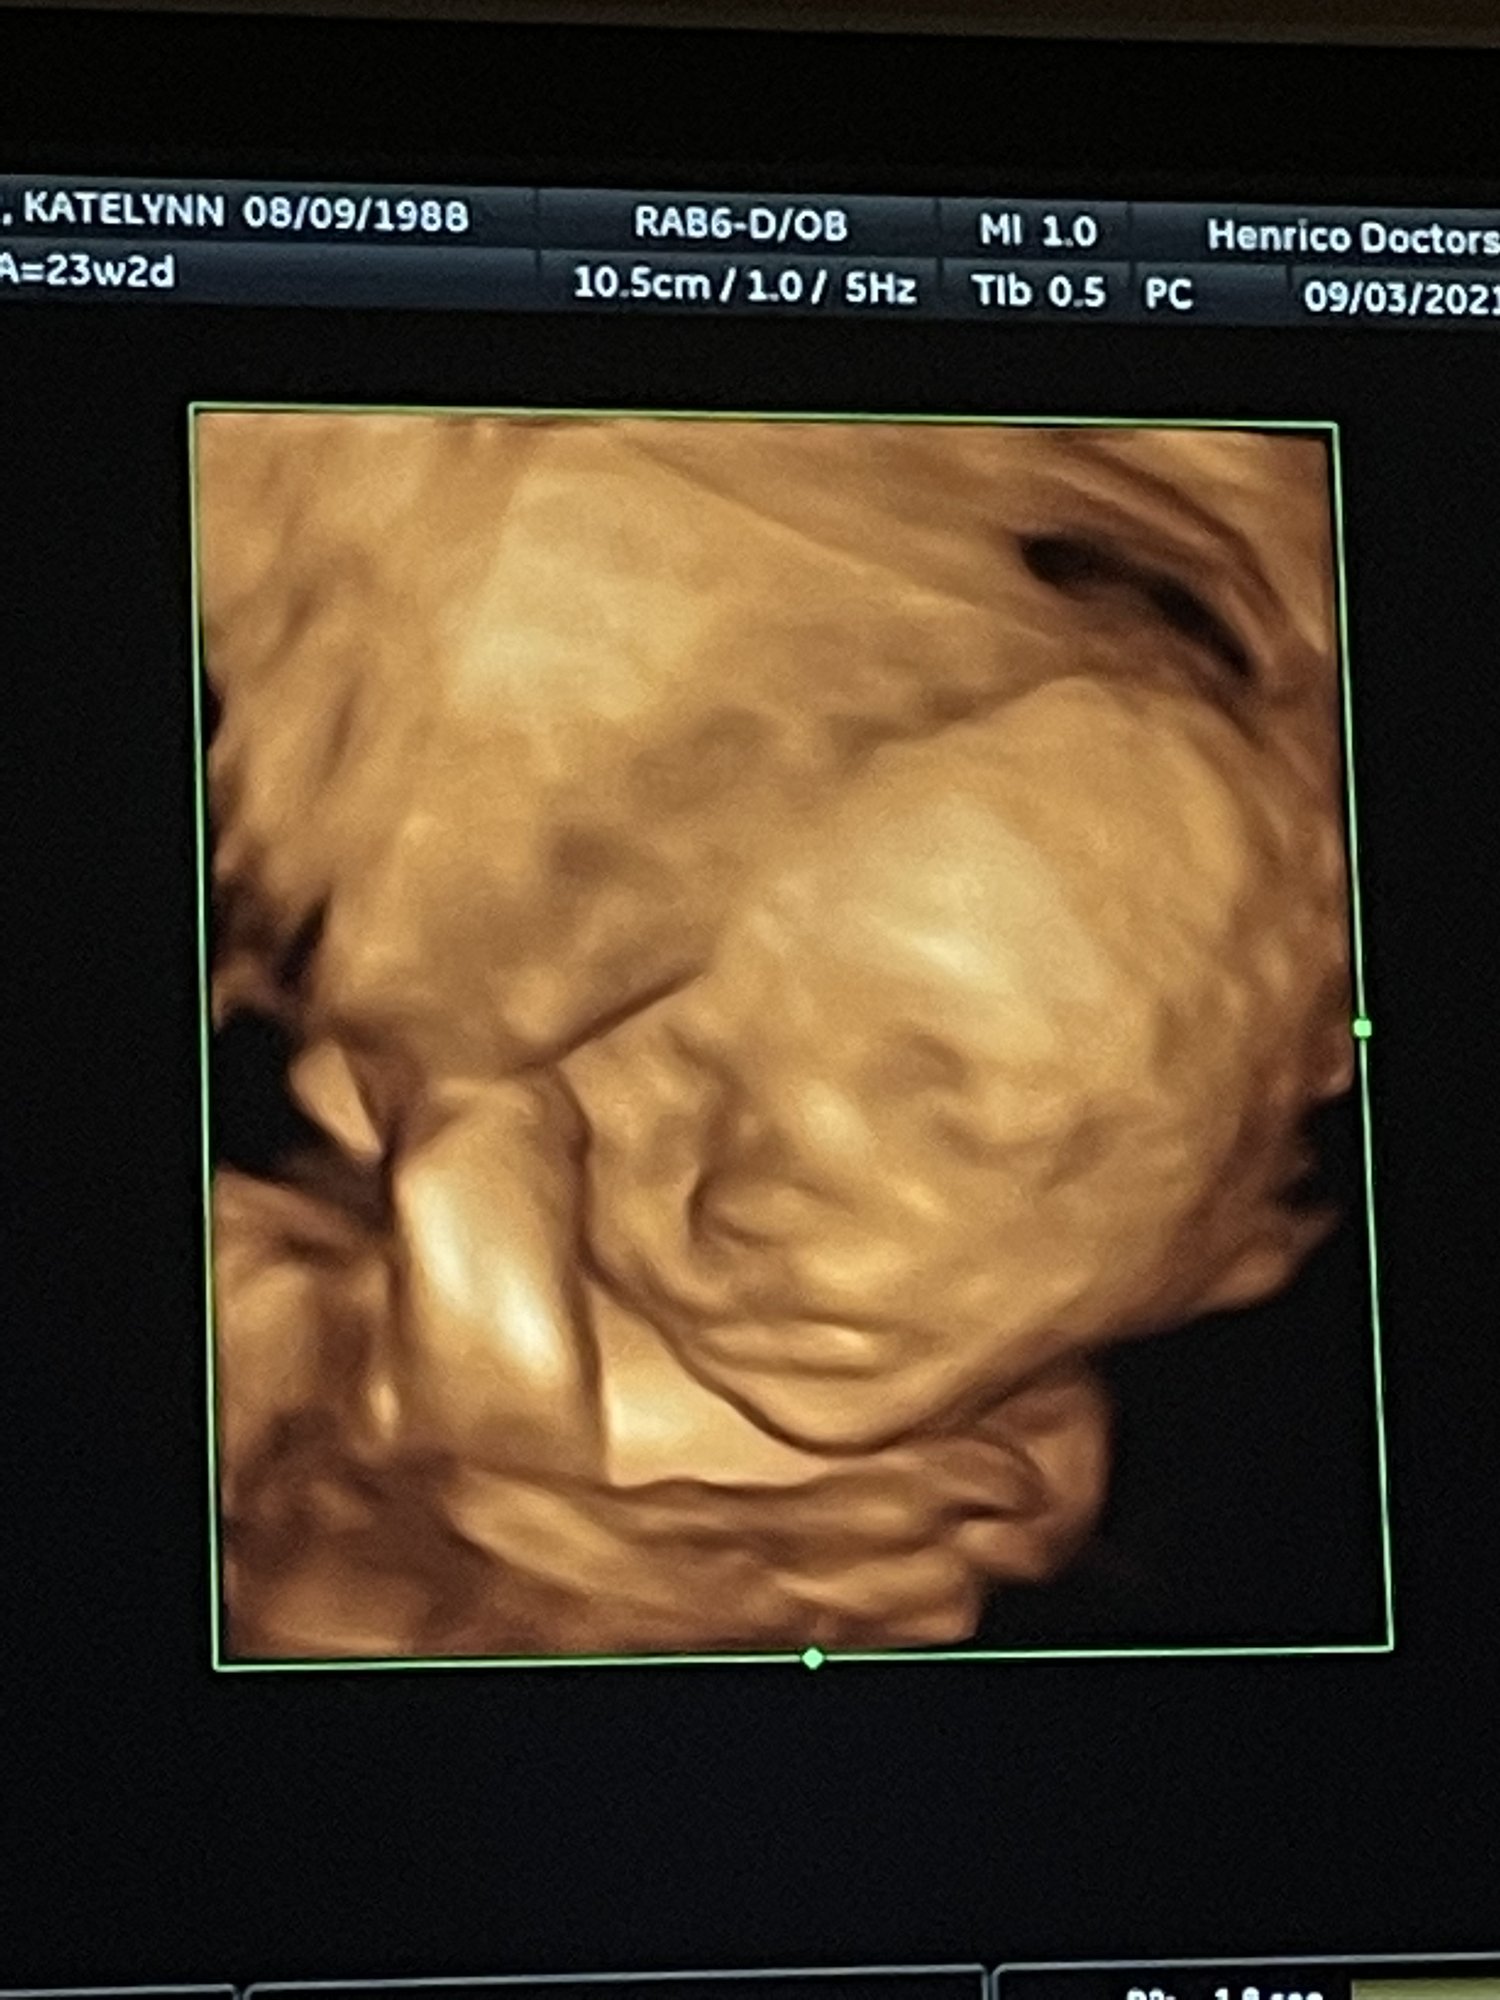

We had our follow up scan today to get the remaining pictures of baby girl's heart - all looks great, thank goodness! She's sucking her thumb here. She was still very active OR curled up in a ball and didn't want to move. Stubborn like her mama.